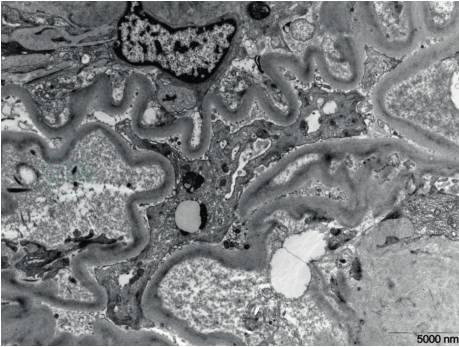

电镜检查可观察到LCDD特征性的超微结构改变,表现为细颗粒状电子致密物质沿肾小管基底膜外侧、肾小球毛细血管基底膜内侧、系膜区、Bowman囊壁及小血管壁沉积(图2、图3),具有重要诊断价值。疾病晚期,肾间质内亦可见类似颗粒状物质沉积。但是部分早期病例仅可观察到肾小球毛细血管基底膜内侧少量、节段性沉积的颗粒物质,此时尚需结合免疫荧光检查进一步确诊。

图2EM肾小球基底膜(GBM)内侧细颗粒状电子致密物

引自:肾脏病学.第4版.ISBN:978-7-117-30643-0.主编: